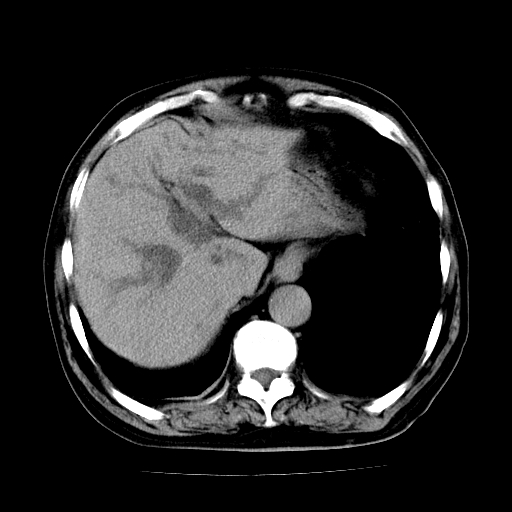

标题: CT25226:男,71岁,皮肤黄染四天。 [打印本页]

男,71岁,皮肤黄染四天。

肝内外胆管及胆总管上段扩张,考虑为梗阻所致,建议mrcp检查。

考虑胆总管癌并肝内外胆管扩张。

胰腺上端胆总管内见软组织影,强化不明显,结合临床,还是考虑低位梗阻性黄疸,胆总管癌可能性大